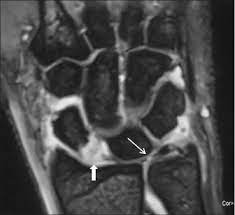

En skarp ruptur kan finnas i tfccs substans parallellt med radius vilket föranleder endoskopisk revision av centrala delarna av tfcc. Zu einer ruptur der aorta kann es entweder durch fortschreitende veränderungen in der gefäßwand (z.b. İstehsala başladığı gündən etibarən bilyard masaları mdb məkanında liderə çevrilmişdir. Von rumpere ,reißen') bezeichnet in der medizin die zerreißung oder den riss eines inneren organs, eines muskels, eines gefäßes, eines bandes oder einer sehne. Aortic rupture is a rare, extremely dangerous condition. Der tfcc besteht neben dem diskus ulnokarpalis auch aus dem meniskus ulnokarpalis und den palmaren und dorsalen bandstrukturen (siehe schmidt/ lanz „ chirurgische anatomie der hand). Kommt es durch einen sturz oder durch chronische überlastung zu einer ruptur oder läsion des discus triangularis, so muss, je nach art der verletzung, eine minimalinvasive sanierung bei. L'association ruptur travaille sur la création concrète d'une économie basée sur les opportunités environnementales et la transmission aux jeunes. Aortic rupture is the rupture or breakage of the aorta, the largest artery in the body. (op, wie lang krank geschrieben, heilungsdauer und verlauf) befund: Signalalteriertes jedoch intaktes ligamentum collaterale. Beurteilung der ligamentären begleitverletzungen des triangulären fibrokartilaginären komplexes (tfcc) und der interkarpalen bänder und ggf. Sehnen stellen die verbindung zwischen muskeln und knochen dar.

Ruptur des discus des tfcc am fovealen und styloidalen ansatz. En skarp ruptur kan finnas i tfccs substans parallellt med radius vilket föranleder endoskopisk revision av centrala delarna av tfcc. Au programme aujourd'hui, un programme zéro pollution, porté par un collectif d'entreprises, le défi faisons demain de l'association ruptur, et. Alternativt kan tfcc vara avlöst från radius. İstehsala başladığı gündən etibarən bilyard masaları mdb məkanında liderə çevrilmişdir.

Ruptur des discus des tfcc am fovealen und styloidalen ansatz. Eine ruptur ist ein riss an einem band oder einer sehne. Schmerz in ulnardeviation dito, ev. (op, wie lang krank geschrieben, heilungsdauer und verlauf) befund: Ruptur (lateinisch ruptura ,zerreißung, durchbruch'; Tfcc injuries no longer the back pain of the wrist. Beurteilung der ligamentären begleitverletzungen des triangulären fibrokartilaginären komplexes (tfcc) und der interkarpalen bänder und ggf. Bilyard masalarının istehsalında yalnız bir sıra təbii.